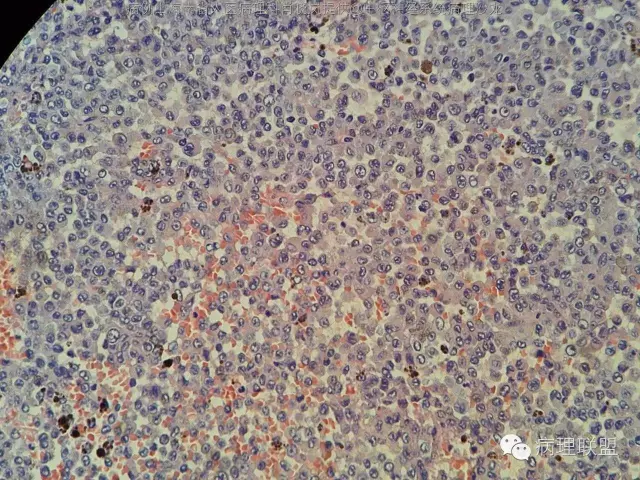

男,36岁。右面部麻木1月余。手术所见:右CPA区见5Ⅹ4cm肿块,灰褐色,血供丰富,质韧,界清。临床诊断:右侧桥小脑角区占位:脑膜瘤。大体检查:灰黑色碎组织一堆,大小2.5Ⅹ2.5x0.5cm,免疫S100,HMB45阳性。Ki67指数低。(病例由海南省人医病理科肖晓岚提供,致谢!)

因为S100,HMB45均阳性,形态也不象色素性神经鞘膜瘤,还是要考虑黑色素的肿瘤吧。S100广泛的阳性,EMA,pR不阳,不支持脑膜瘤吧@福建医大附一病理.王行富

@海南省人医病理科肖晓岚 嗯,黑色素细胞肿瘤,核分裂计数?

罕见吧,一张片都数完了,也没见一个确定的核分裂@福建医大附一病理.王行富

不过,有不少的炎症细胞,中粒比较多

@海南省人医病理科肖晓岚 那就黑色素细胞瘤